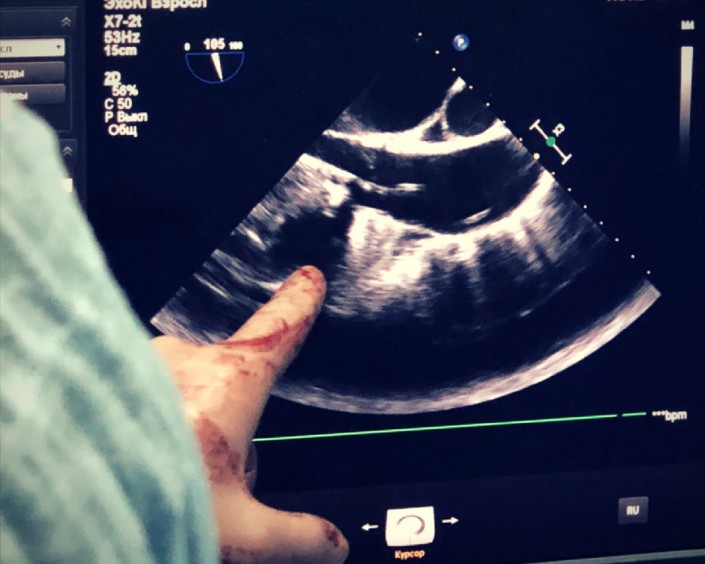

Снова делаем снимки и через рентген проверяем, как действует наша установка.

Далее производим несколько снимков, с помощью которых мы смотрим, куда и как движется катетер с клапаном.